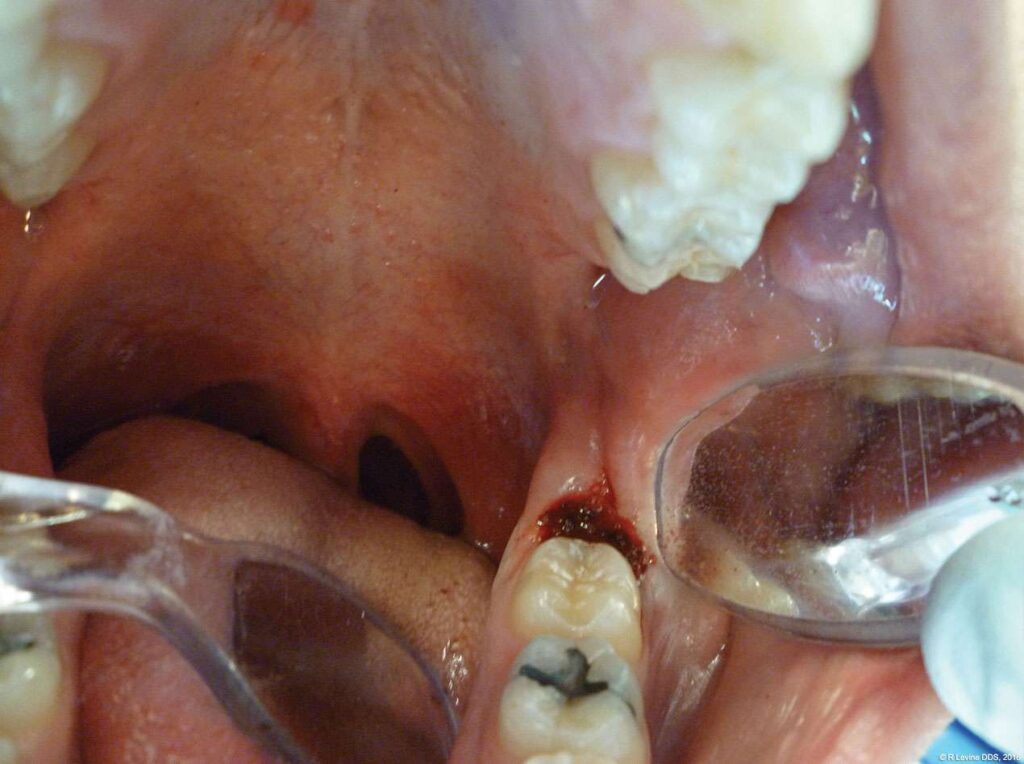

- Additional tissue around the primary surgical site was superficially ablated to “feather out” the wound and make the treated area blend with the healthy gingiva better (Figure 7).

- After the removal of lesion, a periodontal tip was placed approximately 1 mm from the base of the pocket to decontaminate the sulcus area. Laser energy was administered using horizontal movements along the entire distal sulcular aspect.

- Finally, the laser was defocused by moving the handpiece farther away from the surgical area and additional hemostasis was created. No suturing or dressing was needed and the wound was left to heal by secondary intention.